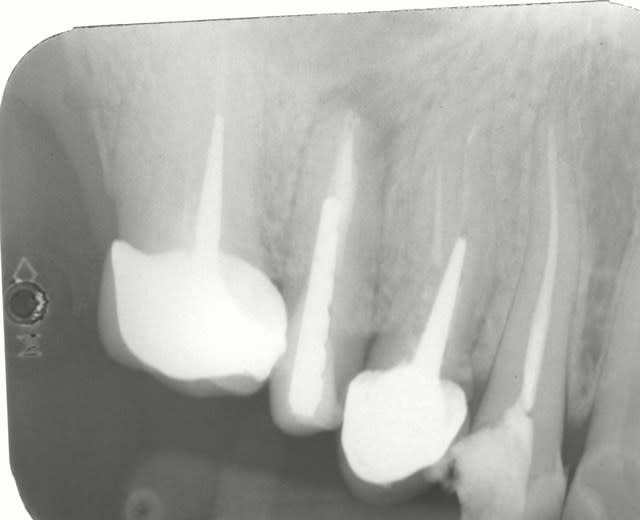

Suite a la demande de HODINA:

j ai retrouvé un autre cas d'extraction réimplantation .

extraction 2004

controle 2006

je peux convoquer la patiente pour radio si vous voulez voir 2014. ce qui est sur ç est que les dents sont tjs en bouche.

d'ailleur il faudrait que je le fasse car j avais scellé les 2 coiffes solidarisées au temp-bond.Je n avais pas pu les enlever par la suite.erreur.